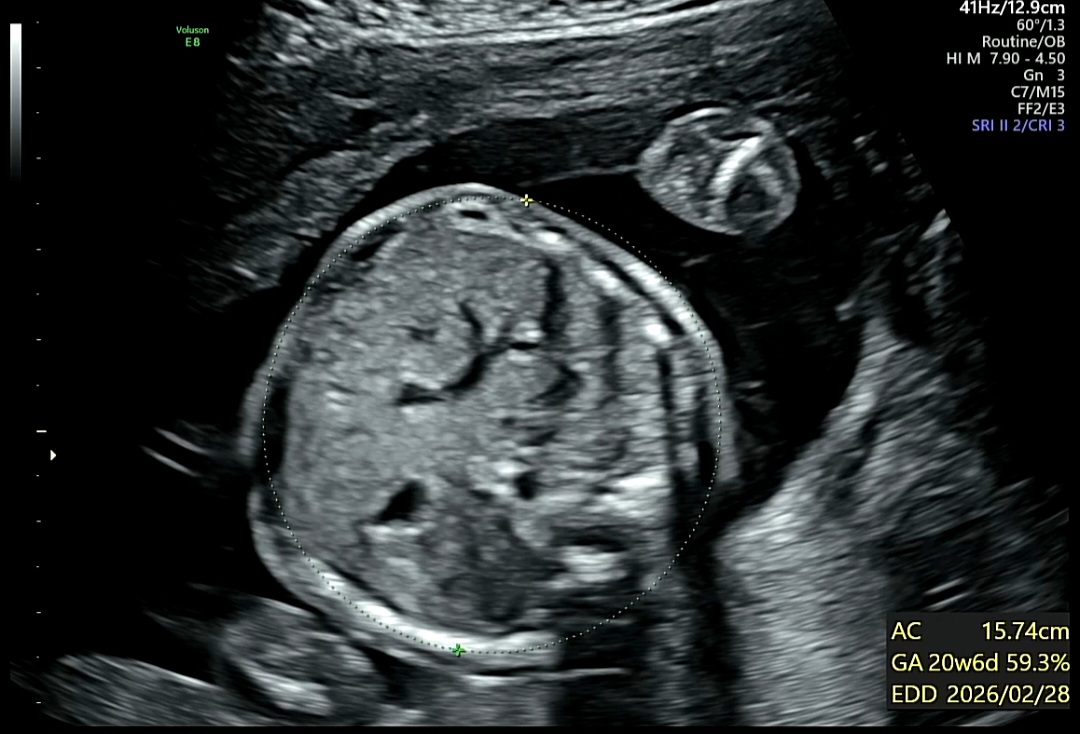

8. 배 둘레 확인

AC (Abdominal Circumference, 복부둘레)

체중 추정 및 영양 상태 확인